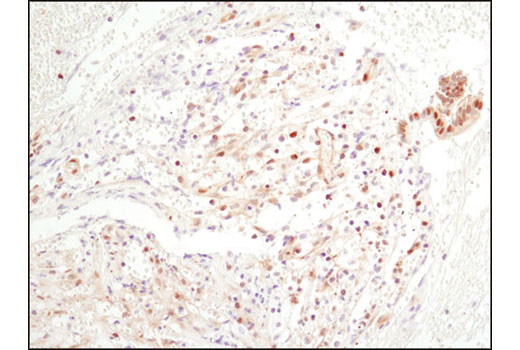

Immunohistochemical analysis of paraffin-embedded human chronic cholecystitis using NF-κB p65 (D14E12) XP® Rabbit mAb.免疫组织化学染色分析石蜡包埋人慢性胆囊炎组织。所用抗体为NF-κB p65 (D14E12) XP® Rabbit mAb。